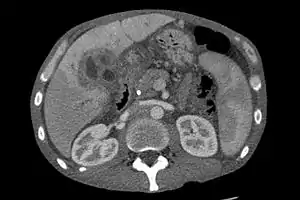

CT scan of a liver with cholangiocarcinoma